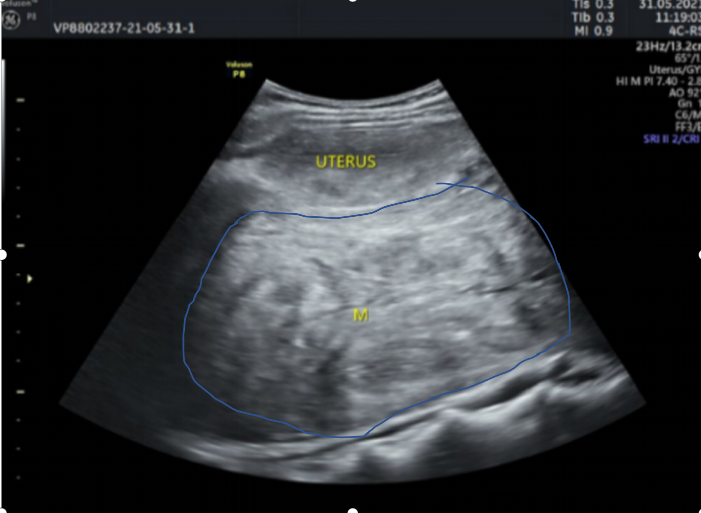

“未见其人,先见其腹”!体重50公斤的黄女士来暨南大学附属第一医院就诊时,她的肚子却巨大得异常突兀,经过全腹CT检查,结果显示:腹盆腔内见一巨大软组织肿块影,大小约22cm×10cm×28cm。子宫后发盆腹腔探及一实性光团,考虑盆腹腔巨大实性占位病变。抽血检查显示,包括肿瘤标记物均正常。

术前彩超检查,子宫后方显示有巨大肿物